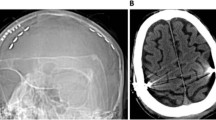

Transcranial direct current stimulation

TDCS was applied according to the international guidelines of Antal et al.40 and performed online during task performance using a battery-powered direct current stimulator (NeuroConn DC-Stimulator plus) with two electrodes (5 ×7 cm2) in sponges soaked with sodium chloride (0.9 %). The anode was placed with the long side horizontally over F3, F7, and T3 of the 10–20 EEG system to optimally cover Broca’s area41, and the cathode supraorbitally on the right hemisphere (FP2), also with the long side horizontally (Fig. 2). Direct current was applied at an intensity of 2 mA for a duration of 20 min with a fade-in and fade-out of 10 s. In the sham condition, the current started but was automatically ramped down after 30 s. Before and after stimulation, participants completed a questionnaire to assess possible side effects (e.g., itching, tingling, headache).